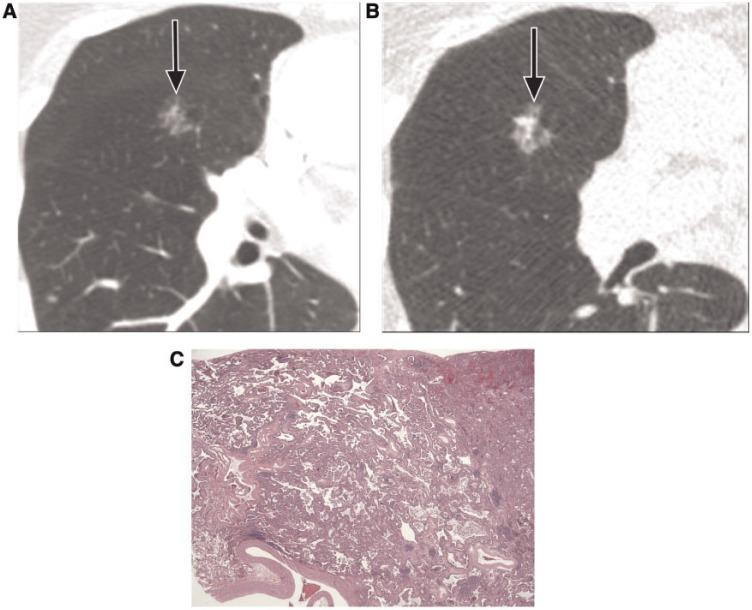

Pulmonary nodules, both solid and subsolid, are common incidental findings on computed tomography (CT) studies. Subsolid nodules (SSNs) may be further classified as either pure ground-glass nodules or part-solid nodules. The differential diagnosis for an SSN is broad, including infection, organizing pneumonia, inflammation, hemorrhage, focal fibrosis, and neoplasm. Adenocarcinomas of the lung are currently the most common type of lung cancer, representing 30-35% of all primary lung tumors, and the subtype of bronchioloalveolar cell carcinoma (BAC) commonly presents as an SSN. In 2011, a new classification system for lung adenocarcinomas was proposed by the International Association for the Study of Lung Cancer, the American Thoracic Society, and the European Respiratory Society. An important feature of the new system is the relinquishment of the term BAC in favor of more specific histologic subtypes. It has been reported that these subtypes are associated with characteristic CT findings. This article reviews the new classification system of lung adenocarcinomas, discusses and illustrates the associated CT findings, and outlines the current recommendations for further diagnosis, treatment, and follow-up of SSNs based on computed tomography findings.

肺部结节,无论是实性还是亚实性,都是计算机断层扫描(CT)研究中的常见偶然发现。亚实性结节(SSN)可进一步分为纯磨玻璃结节或部分实性结节。SSN 的鉴别诊断范围很广,包括感染、机化性肺炎、炎症、出血、局灶性纤维化和肿瘤。肺腺癌是目前最常见的肺癌类型,占所有原发性肺肿瘤的 30-35%,而细支气管肺泡细胞癌(BAC)亚型通常表现为 SSN。2011 年,国际肺癌研究协会、美国胸科学会和欧洲呼吸学会提出了一种新的肺腺癌分类系统。该系统的一个重要特点是放弃 BAC 一词,转而采用更具特异性的组织学亚型。据报道,这些亚型与特征性 CT 表现有关。本文回顾了肺腺癌的新分类系统,讨论并说明了相关的 CT 发现,并概述了基于 CT 发现对 SSN 进行进一步诊断、治疗和随访的当前建议。